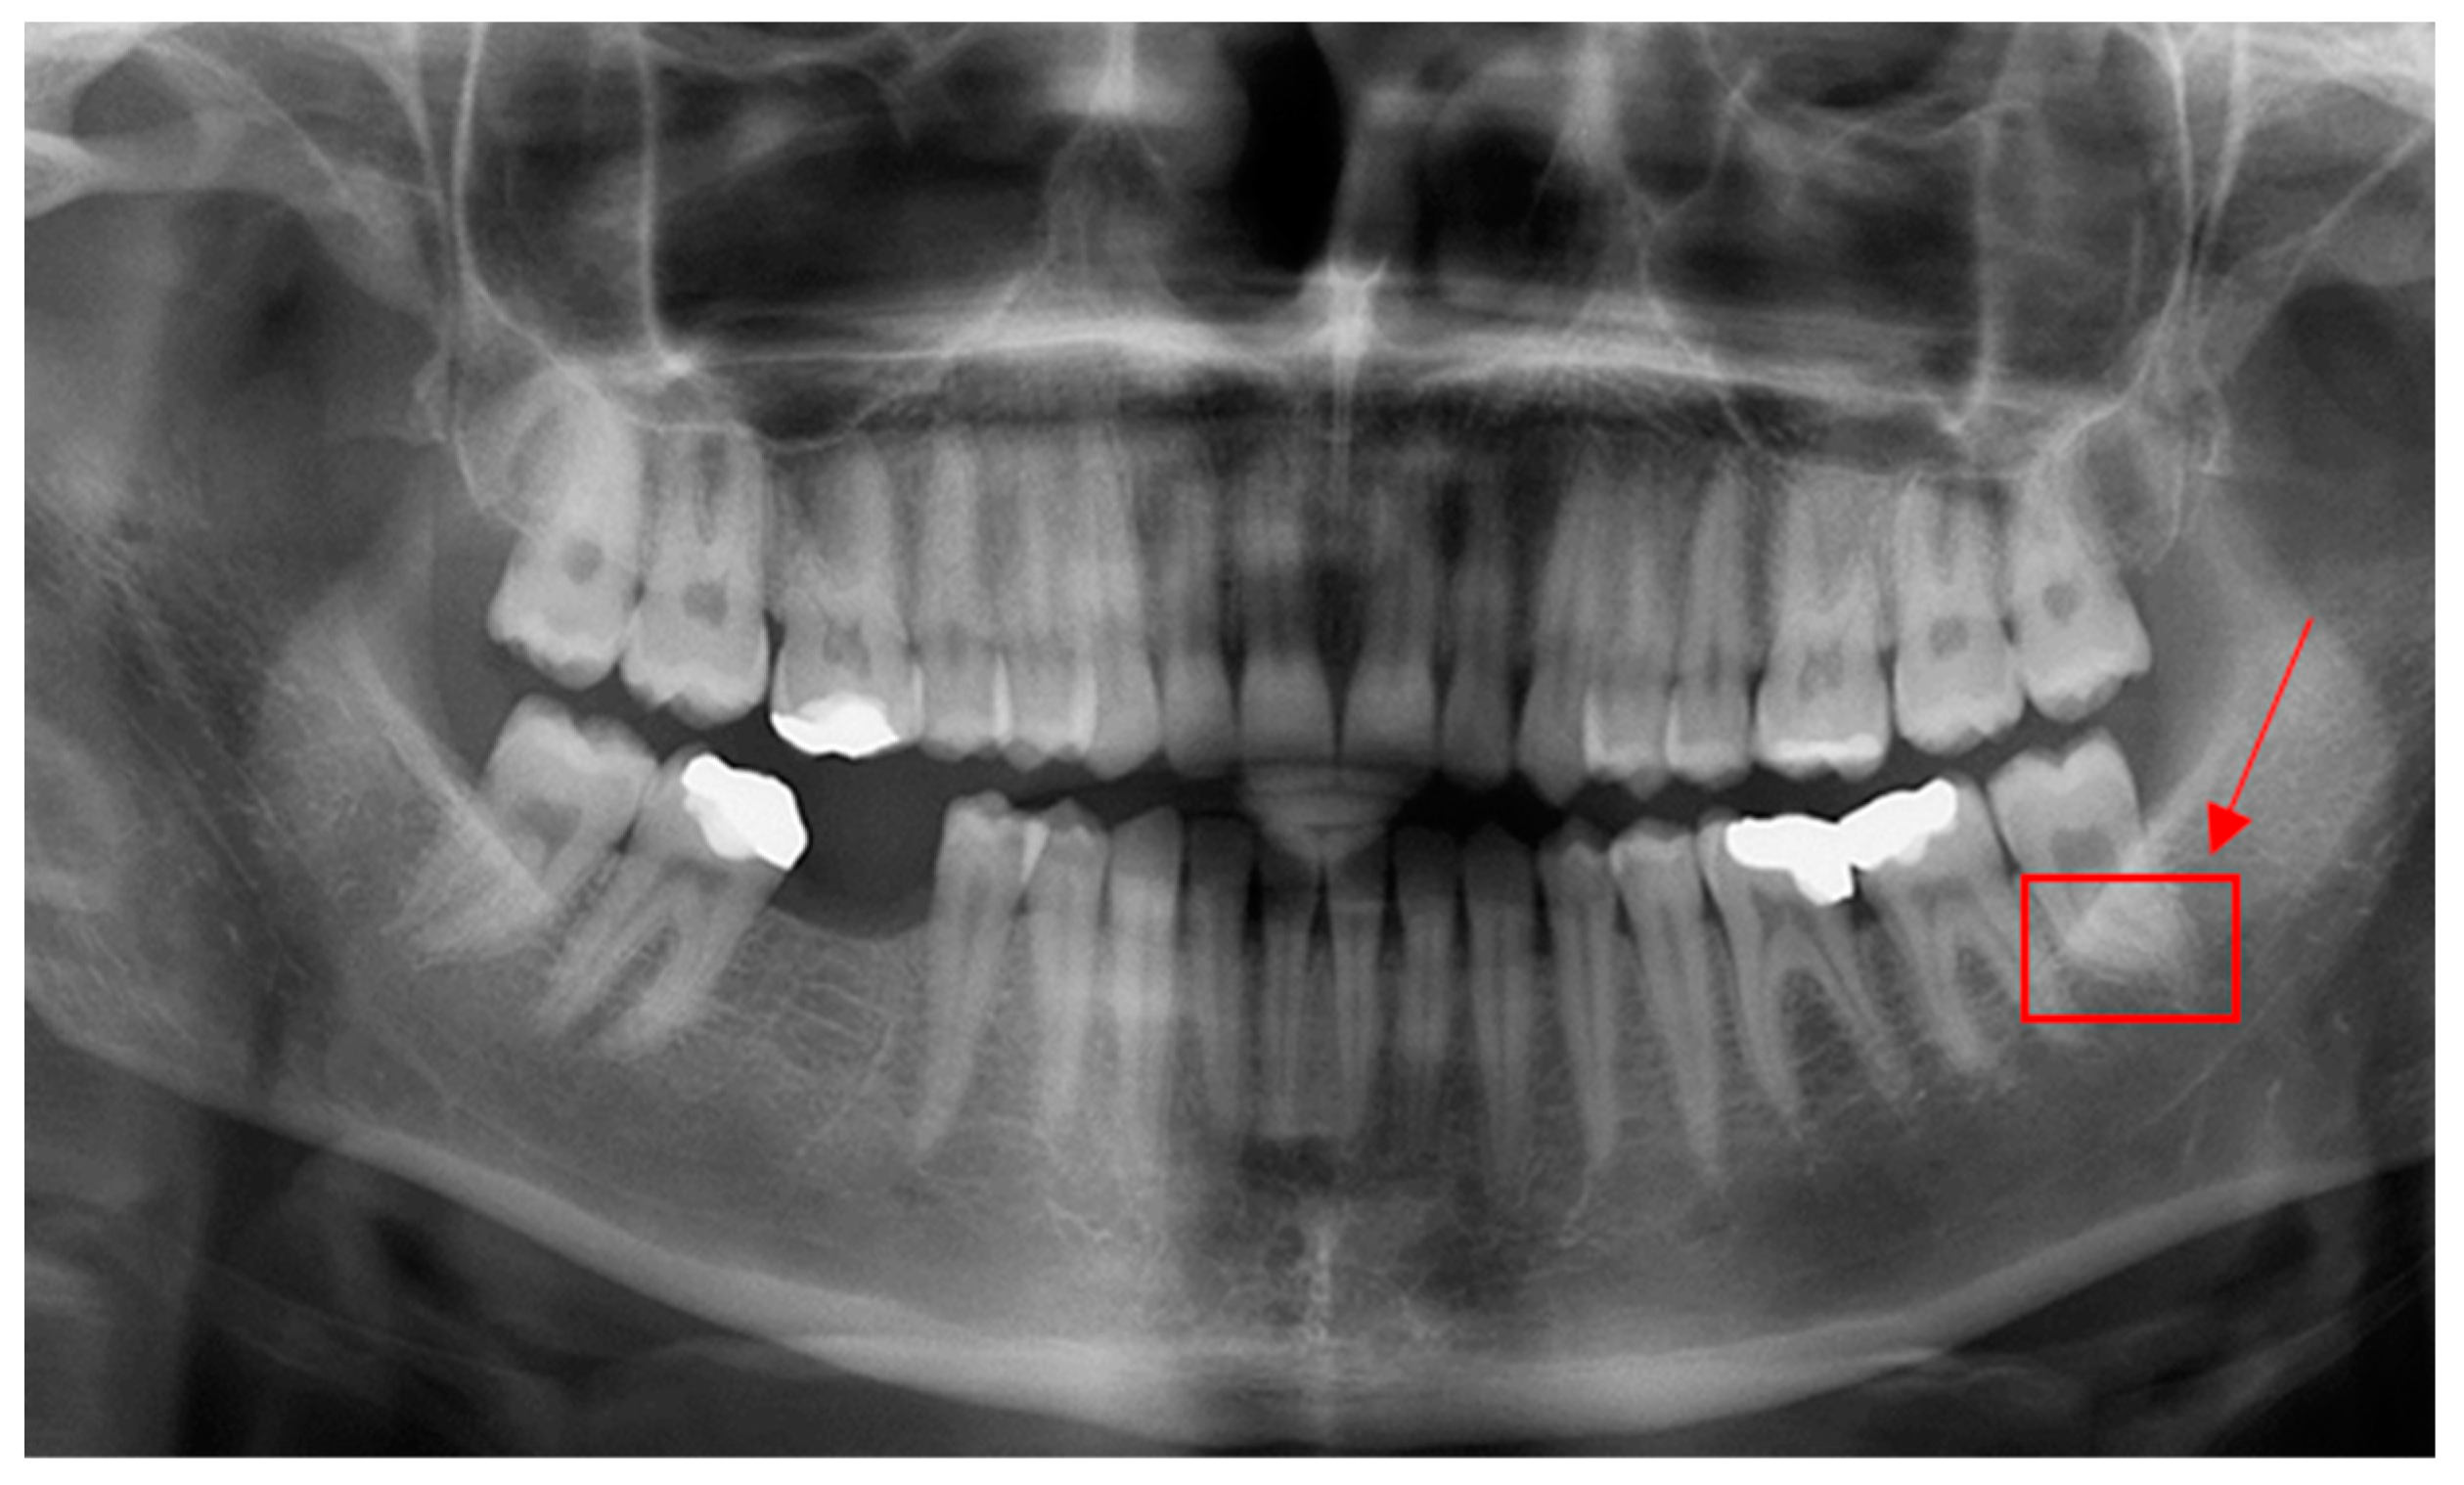

PyTorch and Google CoLab were mainly used to implement deep learning models regarding root dilaceration detection. Figure 2 shows PRs with root dilaceration as an example to show the inputs used for the proposed object detection solution. Before feeding into the deep learning models, data were pre-processed, which included typical operations such as resizing, flipping, normalizing and padding.

Figure 2.

Example PRs with root dilacerations. Red rectangular boxes indicate dilacerated roots that were also used as ground truths. Arrows show dilacerated roots.